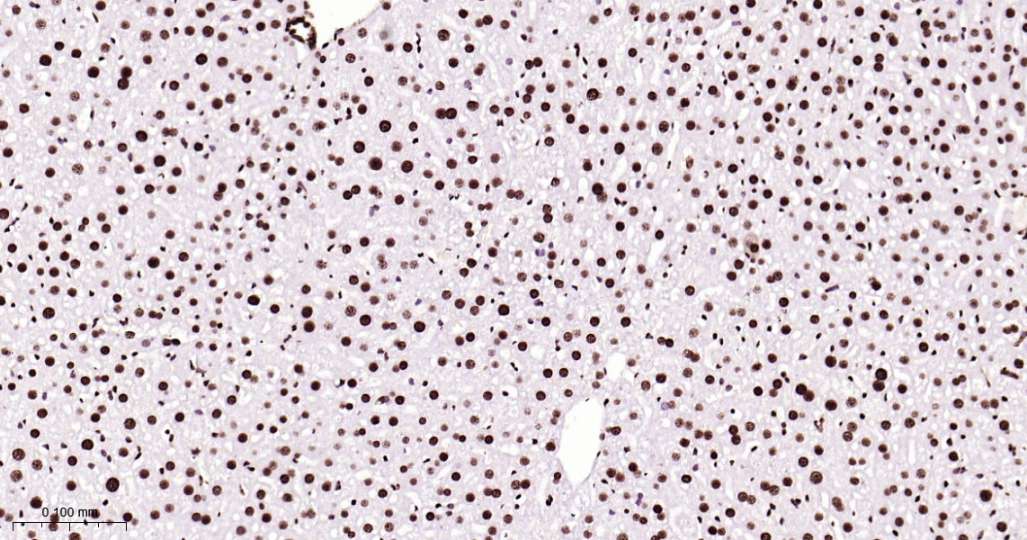

Immunohistochemical analysis of paraffin embedded Mouse liver tissue slide using IHC0566M (Mouse HMGB1 Kit).